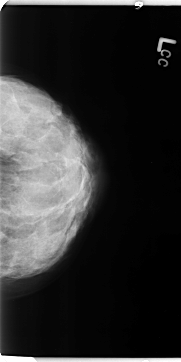

Digital Database for Screening Mammography

Volume: benign_04 Case: B-3112-1

B_3112_1.LEFT_CC

LEFT_CC LINES 4704 PIXELS_PER_LINE 2352 BITS_PER_PIXEL 12 RESOLUTION 50 NON_OVERLAY

FILE: B_3112_1.RIGHT_CC.OVERLAY

TOTAL_ABNORMALITIES 1

ABNORMALITY 1

LESION_TYPE CALCIFICATION TYPE PLEOMORPHIC DISTRIBUTION REGIONAL

ASSESSMENT 4

SUBTLETY 3

PATHOLOGY BENIGN